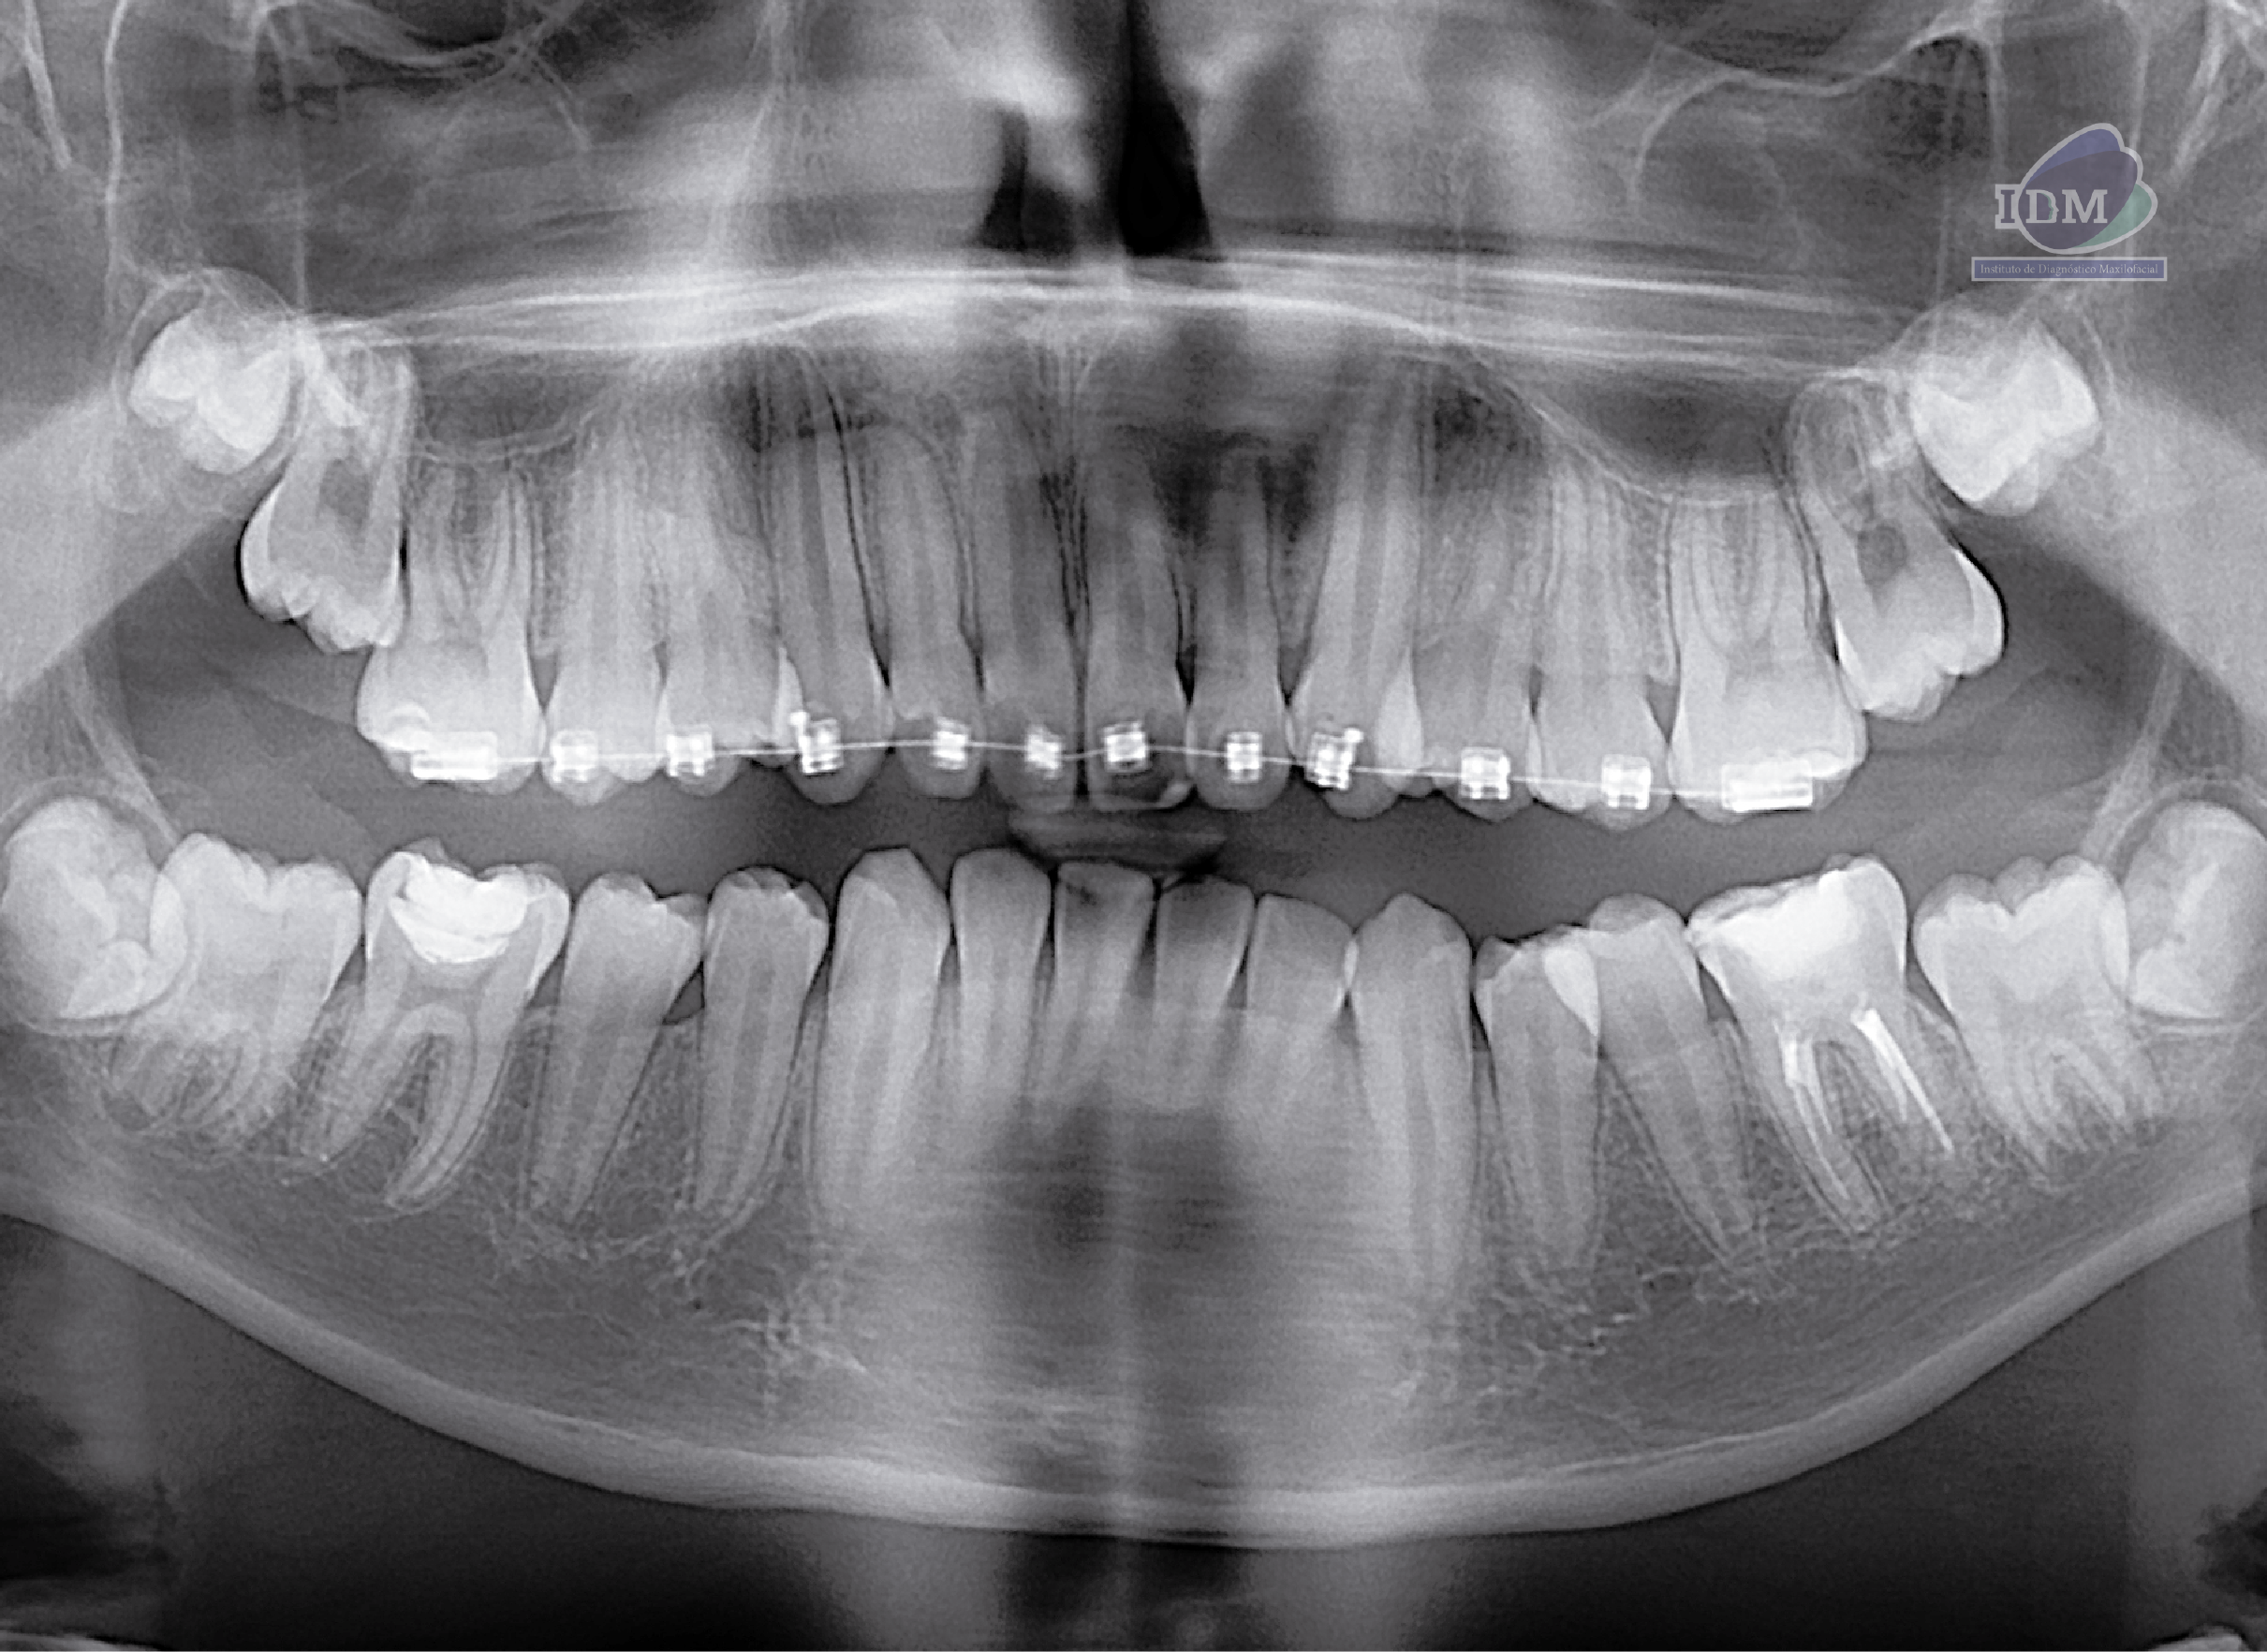

Radiografia Panorámica

En la radiografía panorámica se observan edentulismo parcial superior e inferior, placa cervical mineralizada generalizada, dispositivo de retención protésica en pieza 35, remanentes radiculares de piezas 32, 31, 41 y 42 con obturación de conductos.